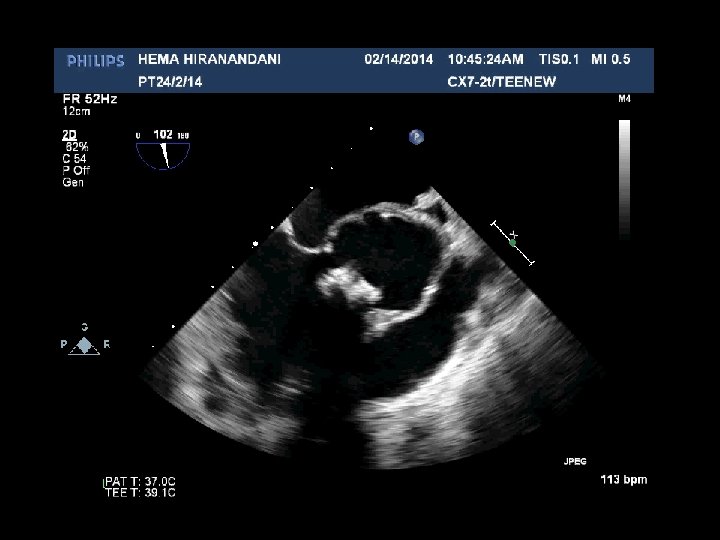

HEMA HIRANANDANI F 57 YRS • • • AVR BIO PROSTHETIC VALVE DEHISCENCE IE MULTIPLE VEGETATIONS ON BIO PRO VALVE AO ROOT ABSCESS SEVERE PARAVALVULAR AR RVSP= 37 mmhg

Hema Hirandani